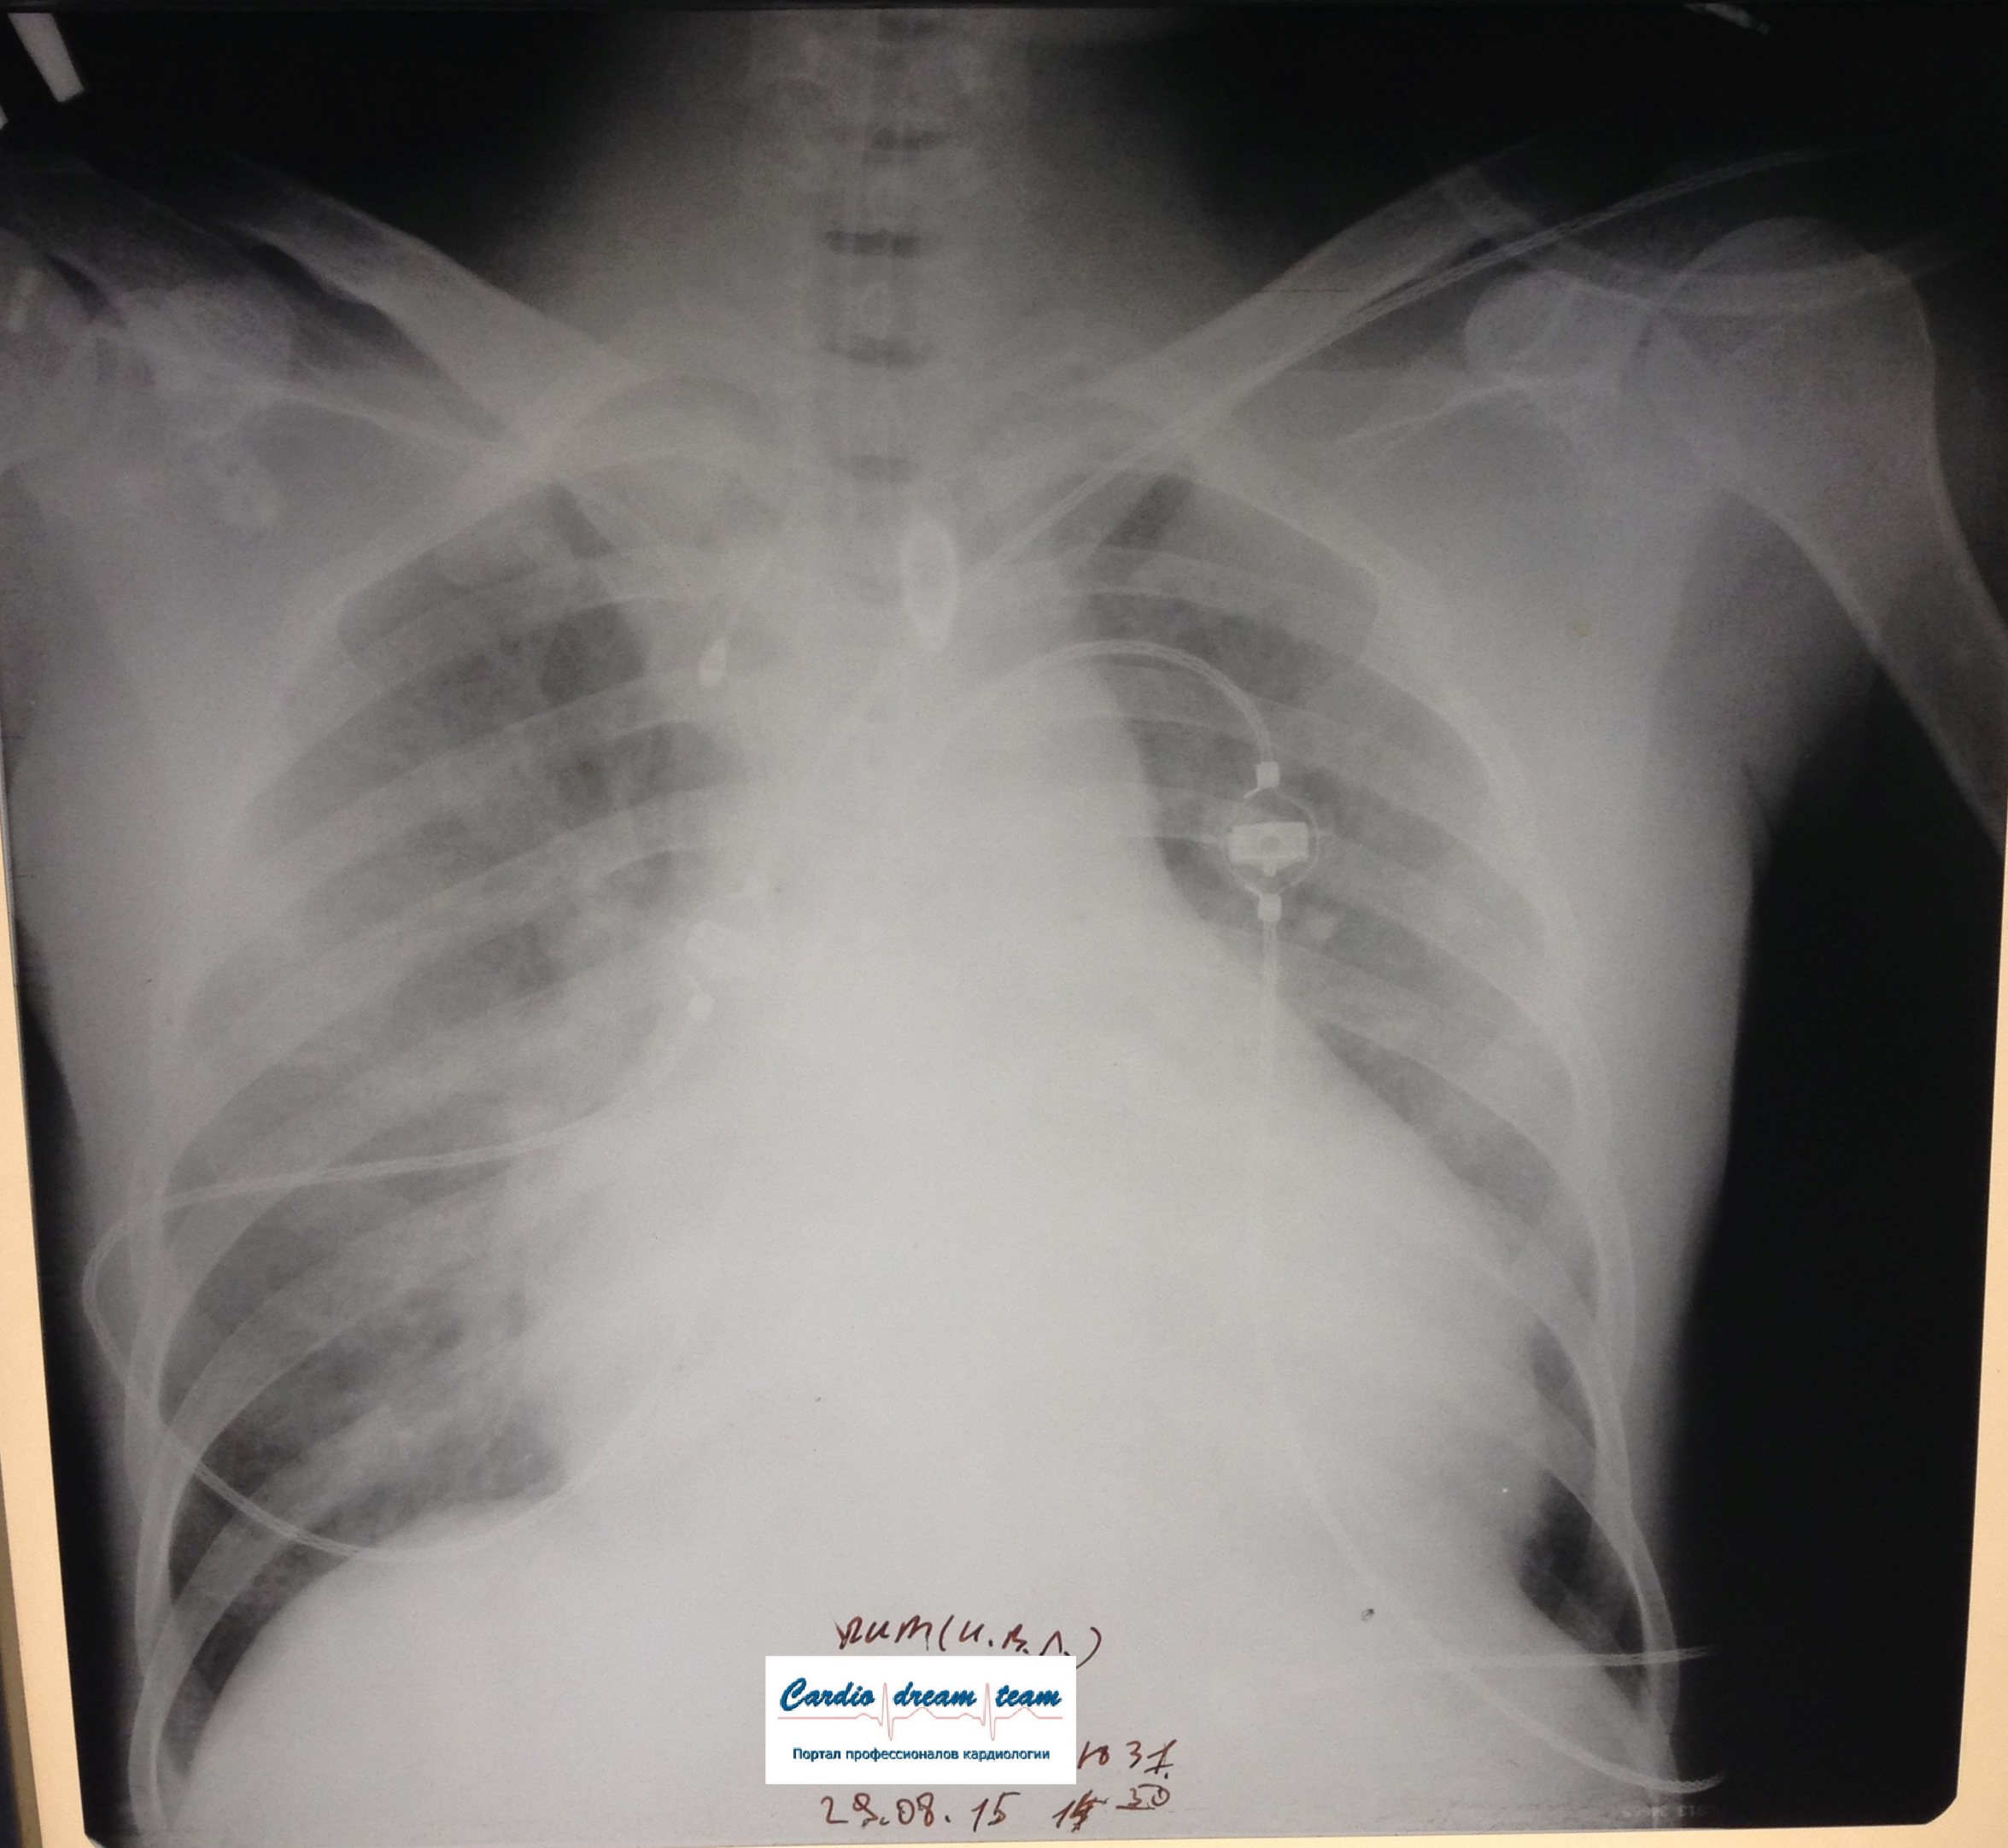

Возникновение и динамика вентилятор - ассоциированной пневмонии.

1-.jpg

1-.jpg [ 713.01 KiB | Просмотров: 53286 ]

2-.jpg

2-.jpg [ 759.1 KiB | Просмотров: 53286 ]